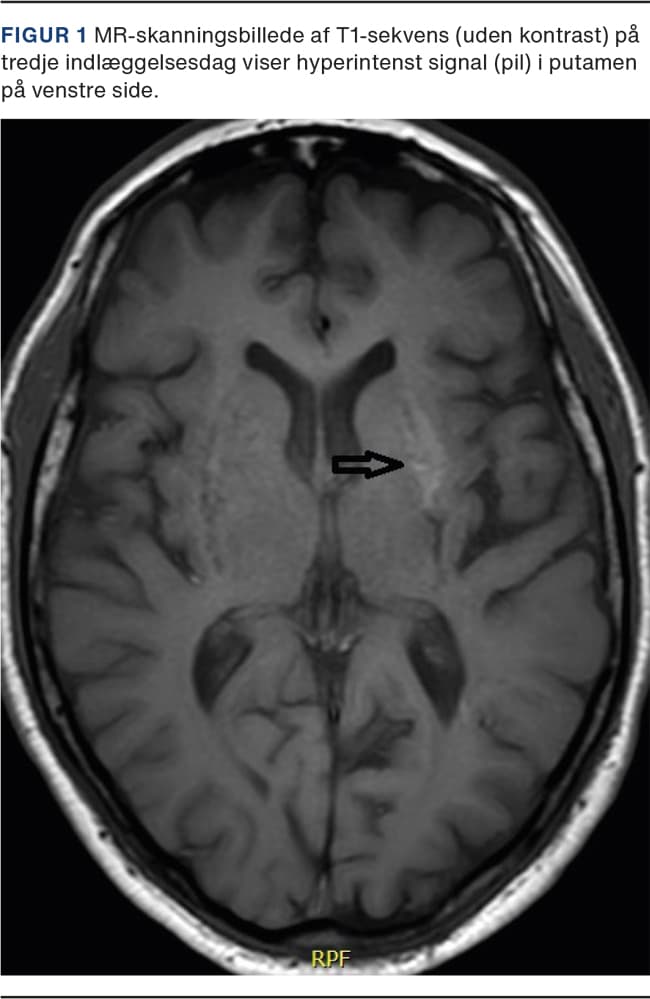

En CT af cerebrum uden kontrast og uden tidligere skanninger til sammenligning viste en diskret øget densitet af venstre nucleus lentiformis. På en MR-skanning af cerebrum sås en hyperintens læsion med målene 2,5 × 1 × 1 cm på en T1-vægtet sekvens af venstre putamen (Figur 1). Differentialdiagnoser ud fra MR-skanning var aflejringer af methæmoglobin, kalcium, mangan eller følger efter hyperglykæmi, leversvigt eller små punktate blødninger. Cerebrospinalvæsken var uden celle- eller proteinforhøjelse, og neurofilament-light chain var normal.

På første indlæggelsesdag påbegyndte man behandling med insulin aspart, og allerede på anden indlæggelsesdag observeredes færre anfald med samtidig bedret glykæmisk kontrol. På tredje indlæggelsesdag påbegyndte man behandling med metformin 500 mg én gang dagligt. Symptomerne var fuldt remitteret på femte indlæggelsesdøgn. Ved opfølgning efter én, 12 og 18 måneder var patienten fortsat i remission. En kontrol-MR-skanning af cerebrum efter 18 måneder viste ligeledes komplet regression af de hyperintense forandringer i venstre basale ganglier.